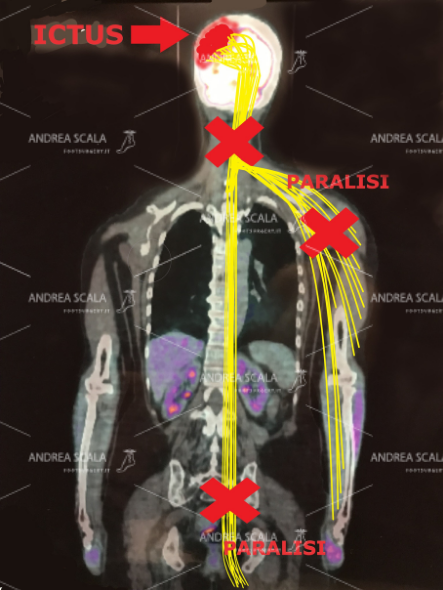

Lo schema mostra in modo elementare che dopo l’ictus le cellule cerebrali muoiono. Dopo l’emorragia (oppure l’ischemia) non avviene il passaggio degli impulsi elettrici dall’altra parte del cervello. Tutti sanno che la parte del corpo opposta all’ictus rimane paralizzata. Si verifica l’emiplegia. Il piede e la caviglia di deformano e non consentono l’appoggio al suolo.

Le facoltà del cervello quali la parola, la memoria, i sentimenti, i ricordi ecc. ecc. riprendono grazie alla parte che non è stata toccata dall’ictus. Dopo la morte dei neuroni (le cellule cerebrali) non c’è rigenerazione verso la periferia. Gli ordini per il movimento degli arti non partono perché non c’è la elettricità. I neuroni che sono nel midollo spinale rimangono privi di ordini superiori. I muscoli degli arti ricevono ordini disordinati e non regolati dal midollo spinale. Per questo motivo alcuni muscoli sono immobili e paralitici e altri sono ipertonici e spastici. Per questo motivo il movimento è inconsulto e disordinato.

L’origine del movimento risiede nella corteccia motoria primaria situata nella area 4 di Brodmann. Dalla corteccia cerebrale partono gli impulsi per le cellule nervose motorie collocate nel midollo spinale (secondo motoneurone). Dopo che l’ictus ha devastato la corteccia cerebrale l’elettricità non si può formare, i neuroni non possono rigenerare, il movimento non può tornare. I professionisti della “riabilitazione” sanno molto bene che la paralisi degli arti non c’entra nulla con la ripresa del cervello. L’ictus ha privato il cervello della origine del movimento. Eppure essi vedono che il malato emiplegico presenta sempre sempre sempre la stessa deformità ma si ostinano nell’attesa di una “rigenerazione” che non potrà mai avvenire.